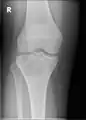

A variety of imaging studies can be used to diagnose chondroblastoma, with radiographs being the most common.[10][8] Laboratory studies are not considered useful.[14] Classical chondroblastoma (appearing on long bones) appears as a well-defined eccentric oval or round lytic lesion that usually involves the adjacent bone cortex without periosteal reaction.[10][13] A sclerotic margin can be seen in some cases.[10][13] For long bone chondroblastomas the tumor is typically contained to the epiphysis or apophysis but may extend through the epiphyseal plate.[10][13] Chondroblastomas are usually located in the medullary portion of bones and can, in some cases, include the metaphysis.[10][13] However, true metaphyseal chondroblastomas are rare and are typically the result of an extension from a neighboring epiphyseal legion.[10][13] Most lesions are less than 4 cm.[10] A mottled appearance on the radiograph is not atypical and indicates areas of calcification which is commonly associated with skeletally immature patients.[10] Additionally, one-third of all cases involve aneurysmal bone cysts which are thought to be the result of stress, trauma or hemorrhage.[10] In cases involving older patients or flat bones, typical radiographic presentation is not as common and may mimic aggressive processes.[10][13]

1. a. X-ray of chondroblastoma of thigh bone near knee -

1. b. CT scan shows chondroblastoma of thigh bone near knee more clearly -

1. c. CT scan of chondroblastoma of thigh bone near knee (cross-section view) -